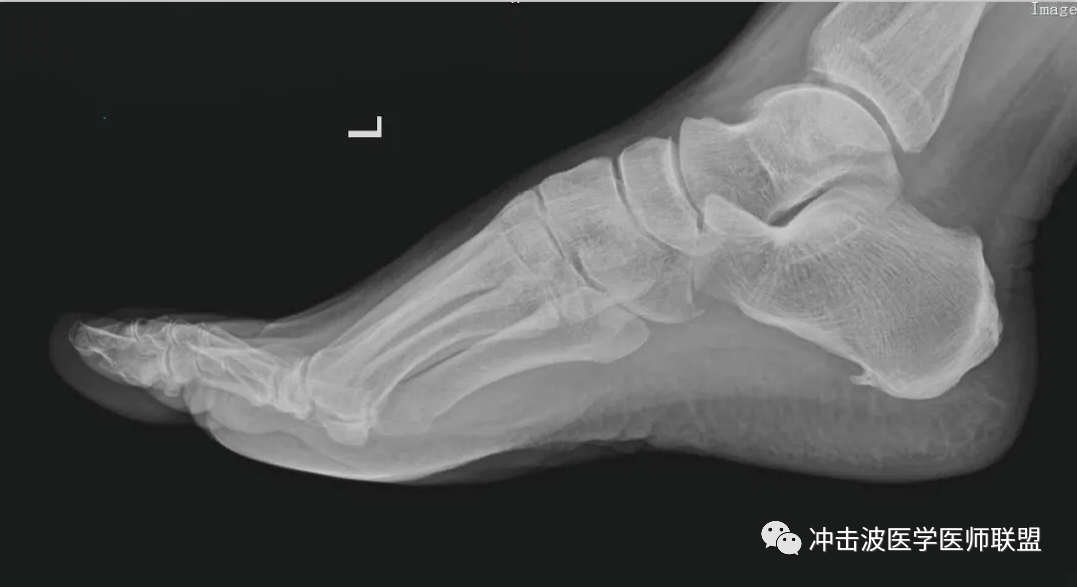

MRI檢查可以見到跟骨跖腱膜止點處的高信號,X線檢查還可見到跟骨下方有明顯的“骨刺”。